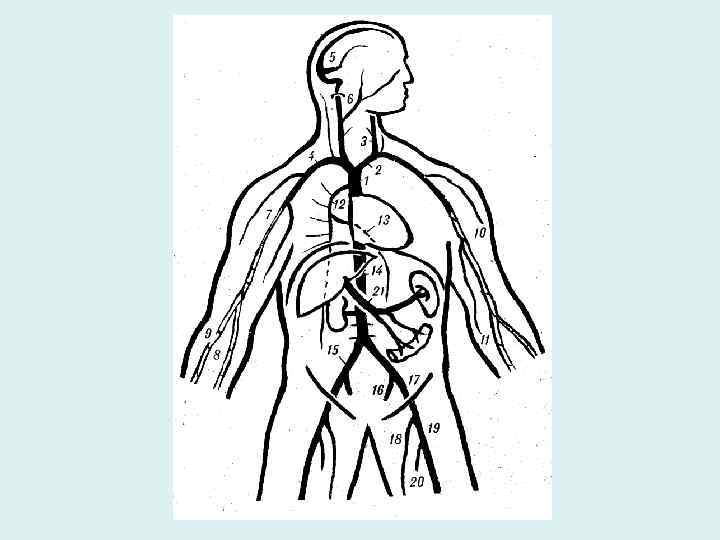

Системы вен большого круга • Система вен сердца • Система верхней полой вены • Система нижней полой вены система воротной вены Межсистемные венозные анастомозы

Верхняя полая вена Собирает кровь от трех групп вен: • Вены головы и шеи • Вены верхних конечностей • Вены грудной и частично брюшной полостей

Нижняя полая вена • Истоки – формируется от слияния общих подвздошных вен • Притоки соответствуют парным ветвям брюшной аорты +печеночные вены • Притоки разделяются на пристеночные и висцеральные

Воротная вена • Собирает кровь от непарных органов брюшной полости • Истоки (корни): селезеночная вена, верхняя и нижняя брыжеечные вены • Притоки: желудочные правая и левая, препилорическая, околопупочные вены